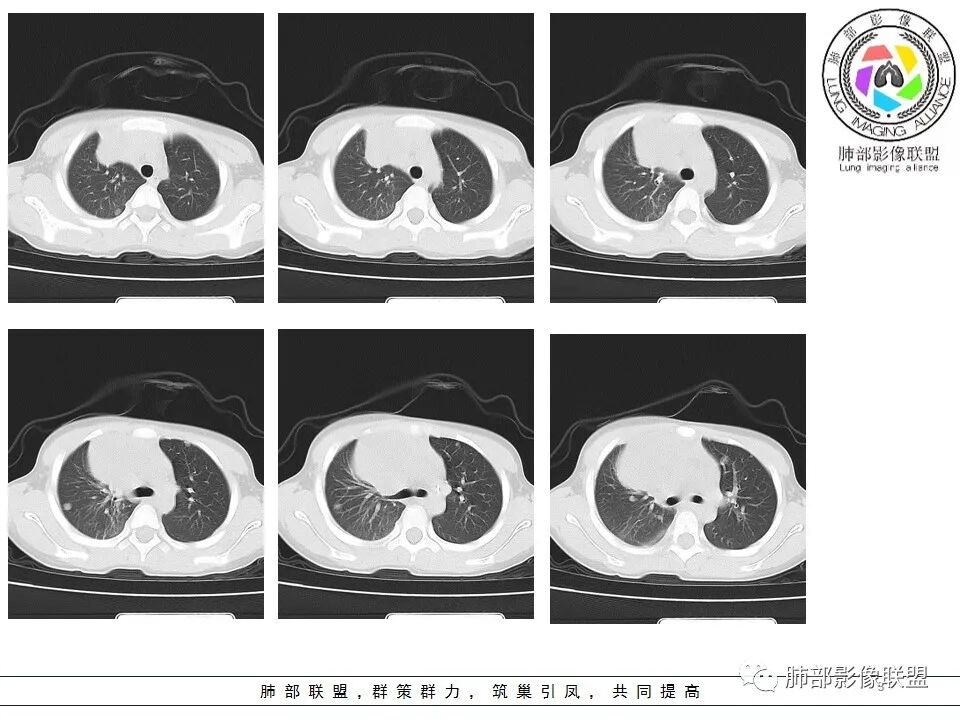

右前纵隔巨大软组织肿块,主要偏向右侧生长,边界不清,密度不均匀,内见大片状低密度坏死区及散在钙化灶,未见骨骼影及脂肪密度影。、双肺随机分布的转移瘤结节,右肺肺不张及右侧胸腔积液,提示恶性肿瘤病变伴双肺及胸膜转移。

精原细胞瘤

临床缺乏特异性,几乎见于男性,一般血清LDH升高,部分β-HCG轻度升高,精原细胞瘤不产生AFP,血AFP升高可考虑非精原细胞瘤或混合生殖细胞肿瘤。影像表现一般肿块巨大,分叶状,边界不清,可浸润性生长,无钙化及脂肪,有纤维分隔,轻中度强化,易转移。

男性,32岁,精原细胞瘤